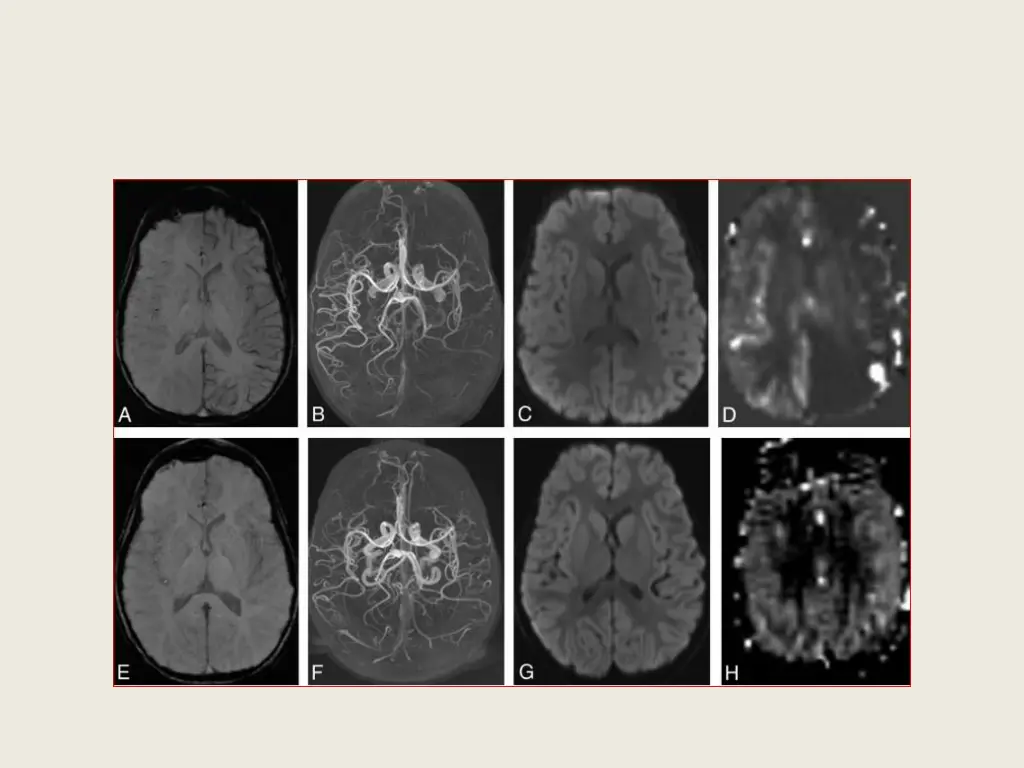

Brain imaging: Brain CT : a new ill-defined hypodencity in the left region of the middle cerebral artery(MCA )as a stroke like area. Brain MRI and MR angiography (MRA) and DWI: Hypoperfusion in left hemisphere, asymmetric venous bulge insensitive weight imaging, and pruning of the left hemisphere peripheral arteries on MR angiography.